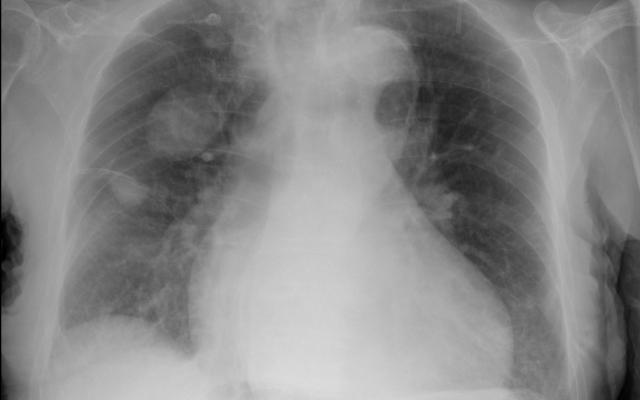

Een 89-jarige man, bekend met cognitieve stoornissen en atriumfibrilleren, werd naar de Spoedeisende Hulp gebracht nadat hij thuis op de grond was aangetroffen. Patiënt zelf had geen klachten. De tractusanamnese leverde geen bijzonderheden op, ook niet op cardiopulmonaal gebied. Bij het lichamelijk onderzoek zagen wij een koortsvrije man met een niet-afwijkende tensie en ademfrequentie. Bij auscultatie van de longen hoorden wij basaal fijne crepitaties over beide longen. Patiënt had pitting oedeem aan beide enkels en een licht verhoogde centraal-veneuze druk. Vanwege de crepitaties lieten wij een thoraxfoto maken (figuur 1). Op de thoraxfoto waren twee bolvormige pulmonale afwijkingen zichtbaar…